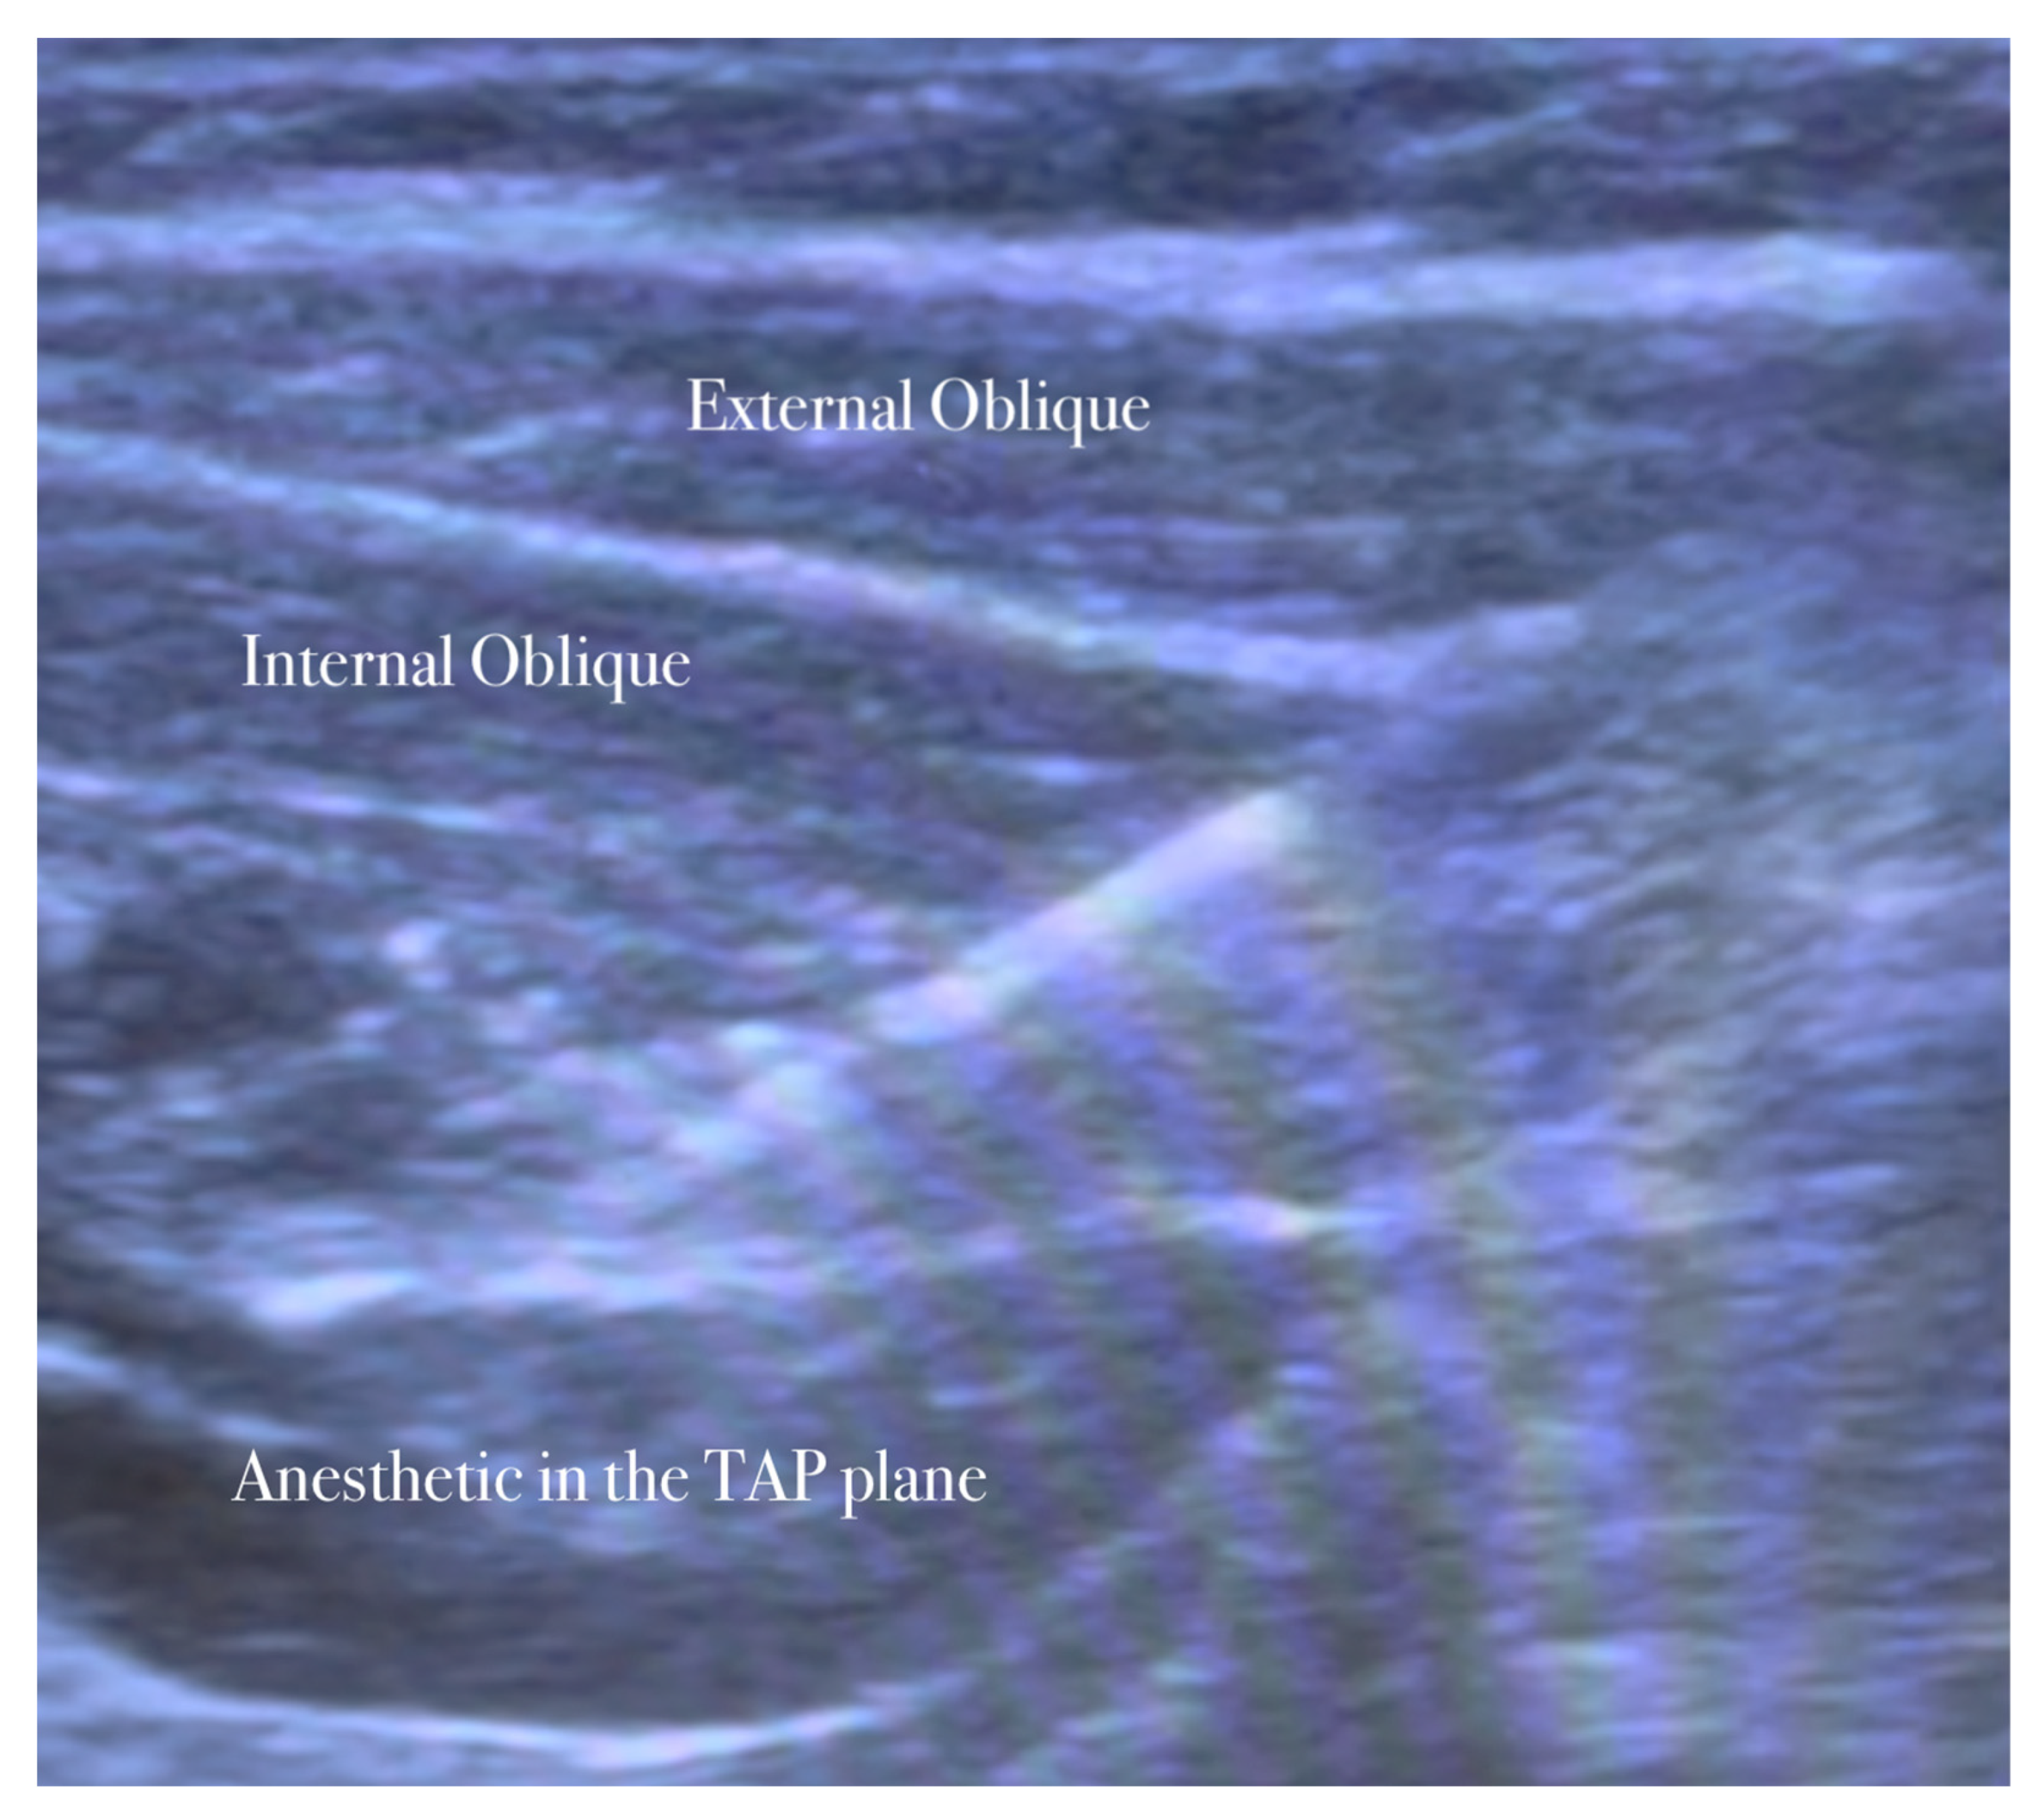

The needle is inserted in the plane in a medial-to-lateral direction; 10 mL of anesthetic (Mepivacaine 10 mg/mL–Ropivacaine 7.5 mg/mL) is injected in the transversus abdominis plane, as seen in Figure 1, Figure 2, Figure 3 and Figure 4.

The anesthetic is injected in the transversus abdominis plane.

5.2. Ilioinguinal–Iliohypogastric Nerves Block

The patient lies in a supine position. The ilioinguinal–iliohypogastric nerves block is performed unilaterally using ultrasound guidance and placed in the transversus abdominis plane. Ilio-hypogastric and ilioinguinal nerves are the terminal branches of the anterior rami of the L1 spinal nerve. They emerge from the upper part of the lateral border of the psoas major muscle; both nerves cross obliquely anterior to the quadratus lumborum and iliacus muscles and perforate the transverse abdominis muscle near the anterior part of the iliac crest. In the anterior abdominal trunk, the nerves travel between the transverse abdominis and the internal oblique muscles [15].

A high-frequency, linear, high-resolution probe is initially kept perpendicularly on the lateral abdominal wall at the midaxillary line between the anterior superior iliac spine and the navel. In this place, the three abdominal muscles are seen below the subcutaneous fat and the plane between the internal oblique, and the transversus abdominis muscle is identified. The peritoneum can be seen as the fascia layer underneath the transversus abdominis muscle. Between the layers of the transversus abdominis and the internal oblique muscle, the splitting of the fascia layer is usually observed. It is on this plane where the ilioinguinal and iliohypogastric nerves pass through. Sometimes, both nerves pierce the internal oblique and appear between the internal and external oblique muscles.